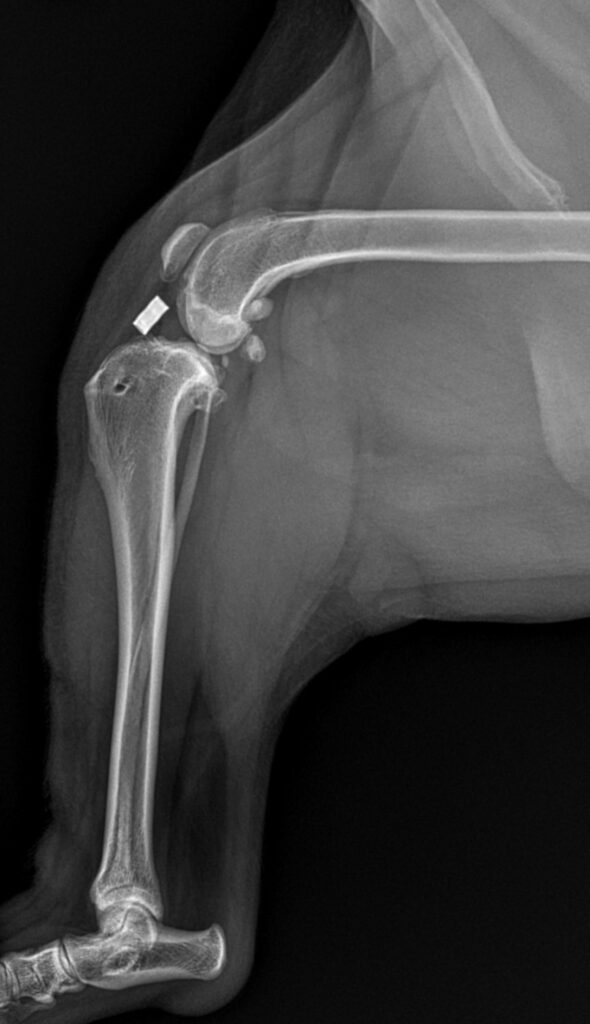

When dealing with a dog that you suspect has an ACL tear, seeking a veterinarian to evaluate them is important. Physical exam findings are correlated with radiographic findings. While ligaments do not show up on plain radiographs (x-rays), there are specific changes that are seen radiographically that can help confirm a diagnosis of an ACL rupture. It is also important to help rule out other conditions with the radiographs, which may have similar clinical presentations.  These other conditions include hip dysplasia, muscular strains, and bone cancer. However, in some cases there may be more than one orthopedic condition at play at the same time. It is not uncommon to reveal hip dysplasia with radiographs, but also find an ACL rupture! Most often, the ACL rupture is what is creating the majority of lameness if the problem presented more acutely.

TPLO PostOp Xray Cary Grove Animal Hospital Cary, IL